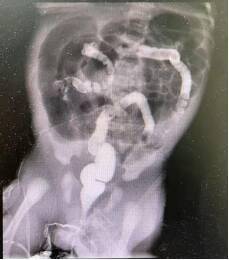

术前X片显示低位肠梗阻